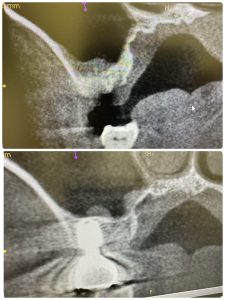

次は、4年ぶり来院😭、デンサーリフト定期検診

異物人工骨は無し!

採血より得られた、濃縮血漿板のみ入れる

あとは、自家骨の圧縮、飛散のみ

グラフトレス サイナスフロアー エレベーション!

パワーtype力の方であり、無養生だが非常に安定🤪

骨がモリモリ、ワイドインプラント径6.5ミリは非常に良い、安定性👌

大臼歯には幅、径ワイドが必須!